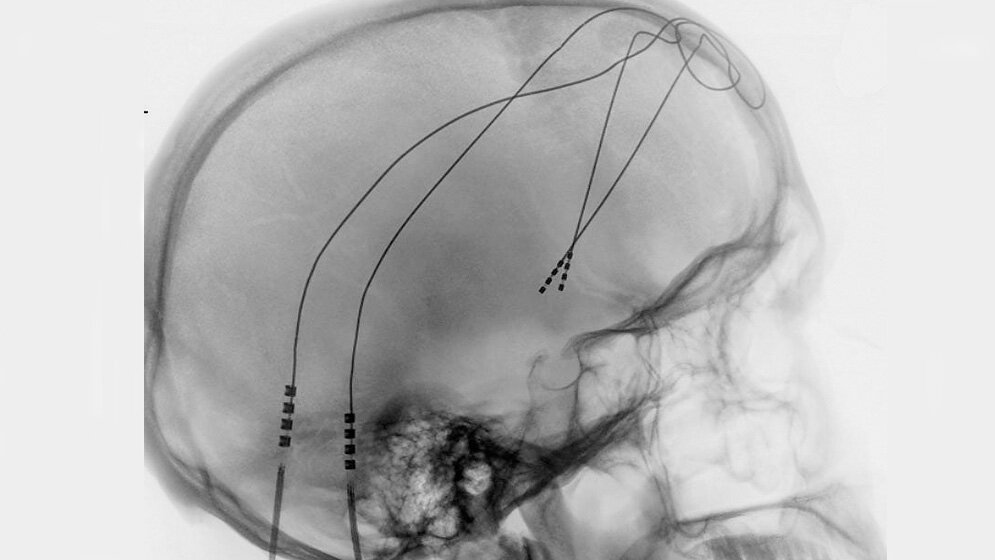

Elektroden im Nucleus accumbens

Elektroden im Nucleus accumbens Uniklinikum Bonn

Seit etwa zehn Jahren wird versucht, diesen depressiven Patienten mit dem Therapieverfahren der tiefen Hirnstimulation zu helfen, die schon seit etwa 20 Jahren mit Erfolg auch in der Neurologie eingesetzt wird. Dazu werden in einer sogenannten stereotaktischen Operation mit Hilfe von bildgebenden Verfahren in unterschiedliche Zielregionen im Gehirn Elektroden eingesetzt. Diese werden mittels unter der Haut verlegter Kabel mit einem Generator verbunden, der ähnlich einem Herzschrittmacher die elektrische Stimulation ermöglicht. Die Wirkung dieser Therapie in verschiedenen Zielgebieten wurde systematisch untersucht und etwa der Hälfte der operierten Patienten wurde damit signifikant geholfen.